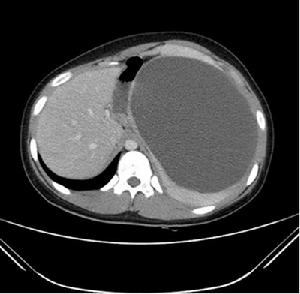

309醫院醫院現代化診療設備配套齊全,擁有核磁共振、螺旋CT、ECT、ET、TCD彩色超聲診斷儀、100毫安X線機、DSA、醫用直線加速器、頭部及體部X刀、動態血壓及動態腦電圖機、骨密度儀等一大批先進醫療儀器設備,總價值過億元,形成了有力的質量保障體系。 醫院始終把醫療質量和醫德醫風建設當做大事來抓,在醫護質量上力求精益求精,在不斷提高醫療服務質量的同時,努力構建良好的醫德信譽,門診就醫環境良好,住院條件優越。